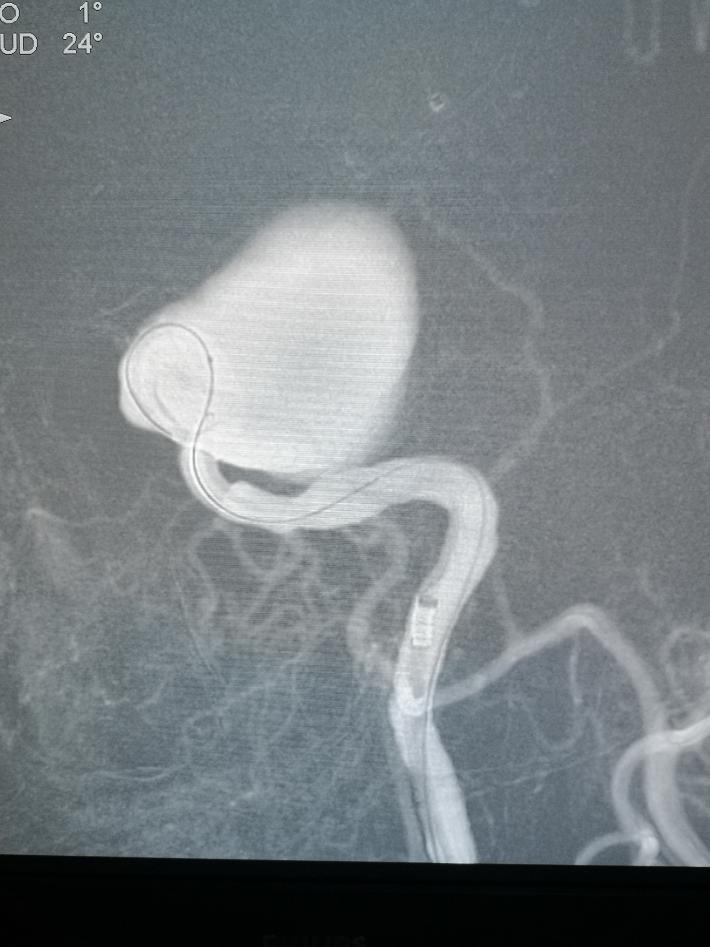

术中见海绵窦水平段巨大动脉瘤,瘤体造影剂明显滞留,且影响远端左侧远端血流。但前交通开放,对侧颈内动脉可完全代偿血流。

术中我们在密网支架导管无法到位的情况下,选择了常规的“支架辅助下动脉瘤介入栓塞术”,动脉瘤顺利得以治疗,由于瘤体巨大,且患者经济原因,无法做到致密填塞。